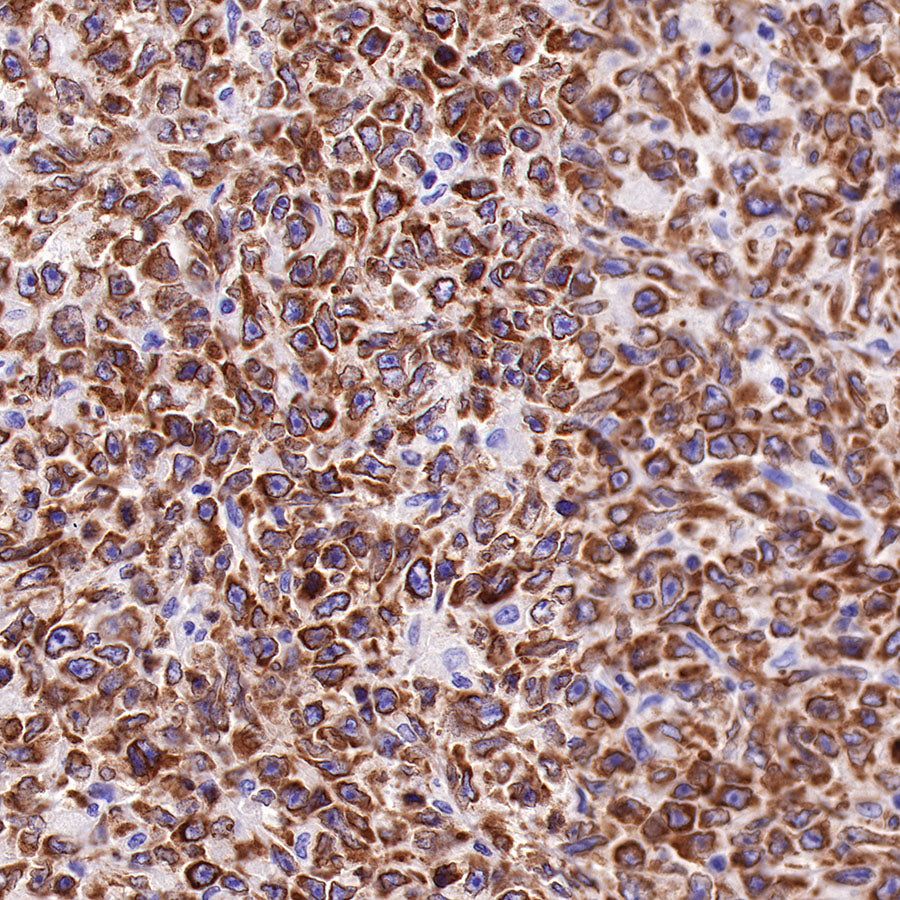

Picture

Picture

Immunohistochemistry